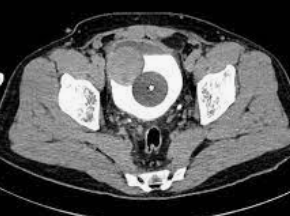

16

Q

40 y/o F

A

Think bladder leiomyoma

Note: Smooth, solid, homogenous soft tissue mass in the region of the trigone (most common location).